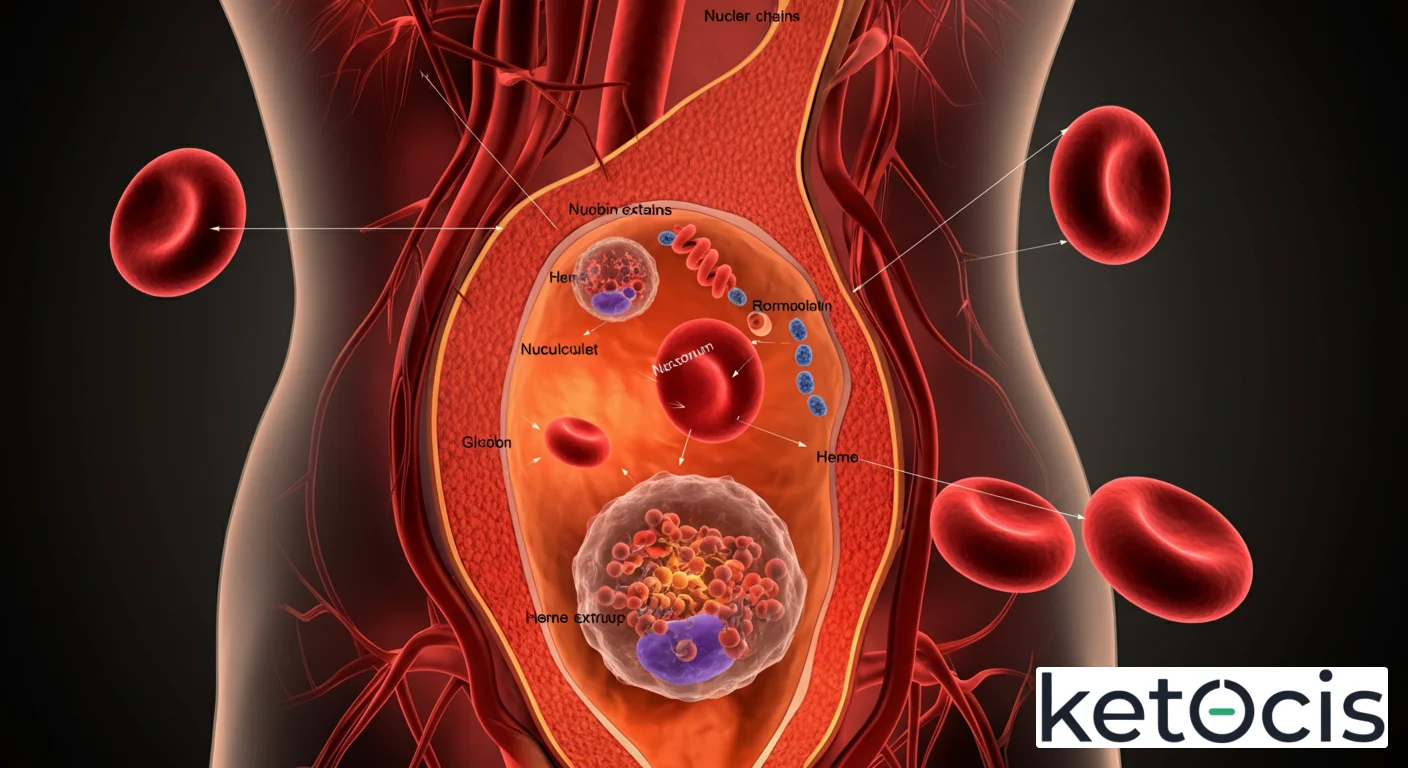

En el vasto y complejo universo de la fisiología humana, cada célula juega un rol insustituible. Entre ellas, los reticulocitos emergen como centinelas dinámicos de nuestra salud sanguínea, actuando como precursores inmediatos de los glóbulos rojos maduros. No son meras células en tránsito, sino indicadores vitales de la capacidad de nuestra médula ósea para responder a las demandas de oxígeno del organismo. Comprender su naturaleza y función es fundamental para desentrañar los misterios de la eritropoyesis y diagnosticar una miríada de condiciones médicas.

Fisiología Molecular: El Viaje de la Célula Joven

El nacimiento de un reticulocito comienza en la médula ósea, el tejido esponjoso que se encuentra dentro de nuestros huesos. Aquí, las células madre hematopoyéticas pluripotenciales dan origen a una serie de precursores, culminando en el eritroblasto ortocromático. Este eritroblasto es la última célula precursora en el linaje eritroide que contiene un núcleo. El proceso clave para la formación del reticulocito es la extrusión del núcleo, un evento dramático y esencial que lo diferencia de sus predecesores.

Una vez que el eritroblasto ortocromático expulsa su núcleo, se convierte en un reticulocito. A pesar de haber perdido su núcleo, el reticulocito aún retiene una cantidad significativa de ARN ribosómico (ARNr) y mitocondrias. Estos orgánulos son cruciales porque le permiten al reticulocito continuar sintetizando hemoglobina y metabolizar energía (aunque de forma limitada) durante su breve período en la circulación periférica. La presencia de este ARNr es lo que le da al reticulocito su característico aspecto reticulado (una red de material granular) cuando se tiñe con colorantes supravitales como el azul de cresilo brillante, de donde deriva su nombre.

El reticulocito pasa aproximadamente 1-2 días en la médula ósea y luego es liberado al torrente sanguíneo. Una vez en circulación, continúa su proceso de maduración final, que dura aproximadamente 1 a 2 días adicionales. Durante este tiempo, el ARNr y las mitocondrias se degradan progresivamente hasta que el reticulocito se convierte en un eritrocito maduro, una célula anucleada, bicóncava, cuya función principal es el transporte de oxígeno. La hormona clave que regula todo este proceso es la eritropoyetina (EPO), producida principalmente por los riñones en respuesta a la hipoxia. La EPO estimula la proliferación y diferenciación de los precursores eritroides, y la liberación de reticulocitos.